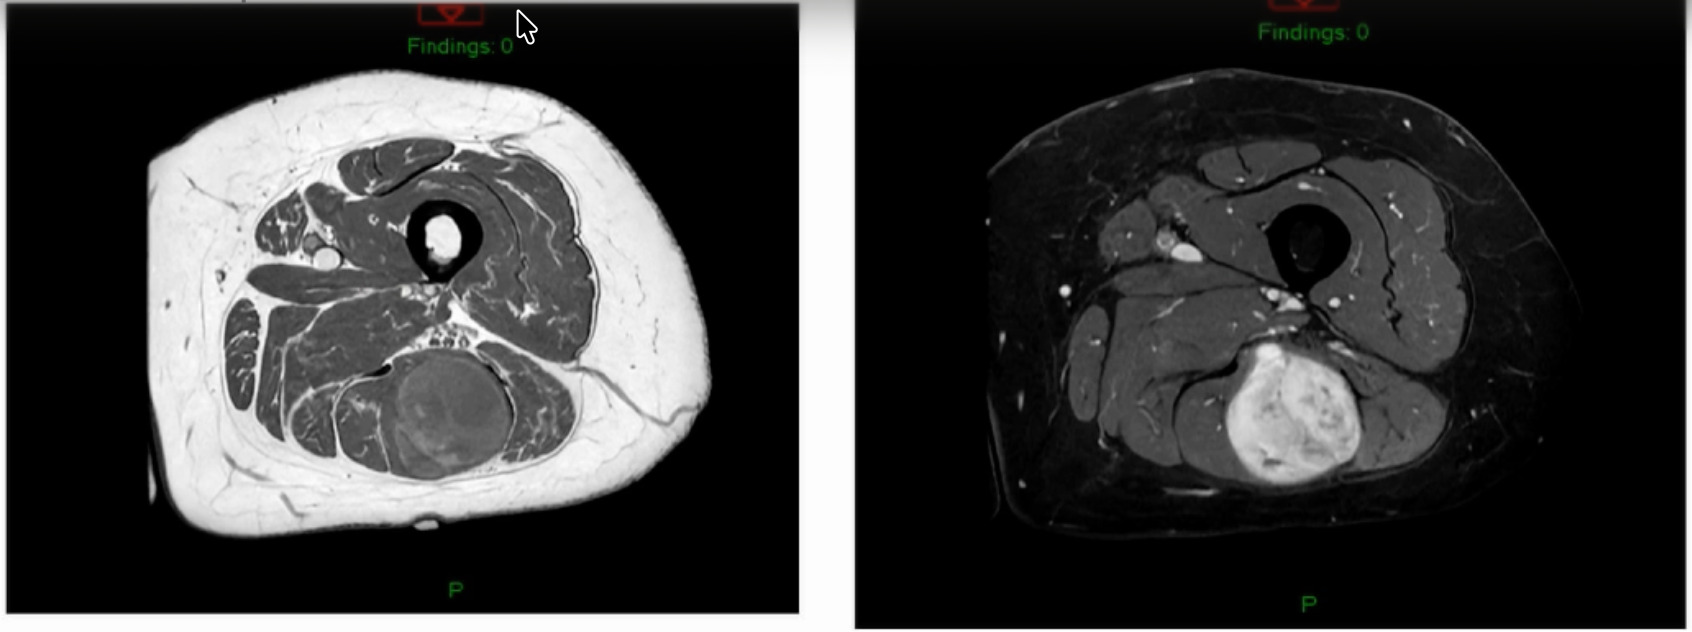

This is a 76-year-old that I just saw this week that had a bump on her thigh annd this is the report (Figure 4).

Unsure what it is? Intramuscular lipoma? Intramuscular lipomas aren’t firm and they aren’t hot. Ultrasound for that? The “gold standard” would be an MRI, not an ultrasound, but they did ultrasound it. The ultrasound came back with, “should get an MRI.” But they biopsied it instead. An MRI was then obtained after the biopsy. (Figure 5)

The biopsy came back as a myxoid fibrosarcoma they biopsied it with a needle, so it’s very hard to tell grade. Additionally, if I’ve got a tumor that’s this big and I’ve got a needle the size of a pin then my sampling error is massive. I don’t ever believe grade off of a biopsy. I just get biopsies so that now I can at least give radiation or do whatever pre-operatively. She is starting her radiation next week for a number of reasons. But she’s got a myxoid fibrosarcoma.